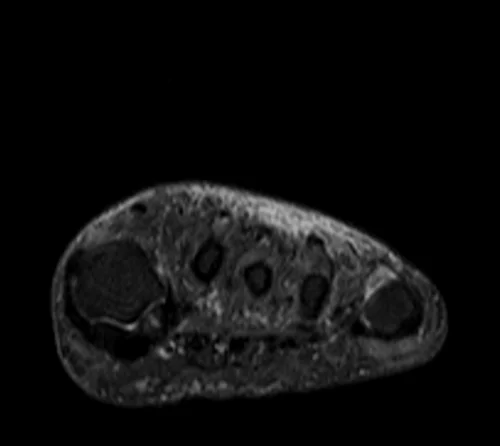

MRI FOOT AXIAL STIR IMAGE 2 - MRI